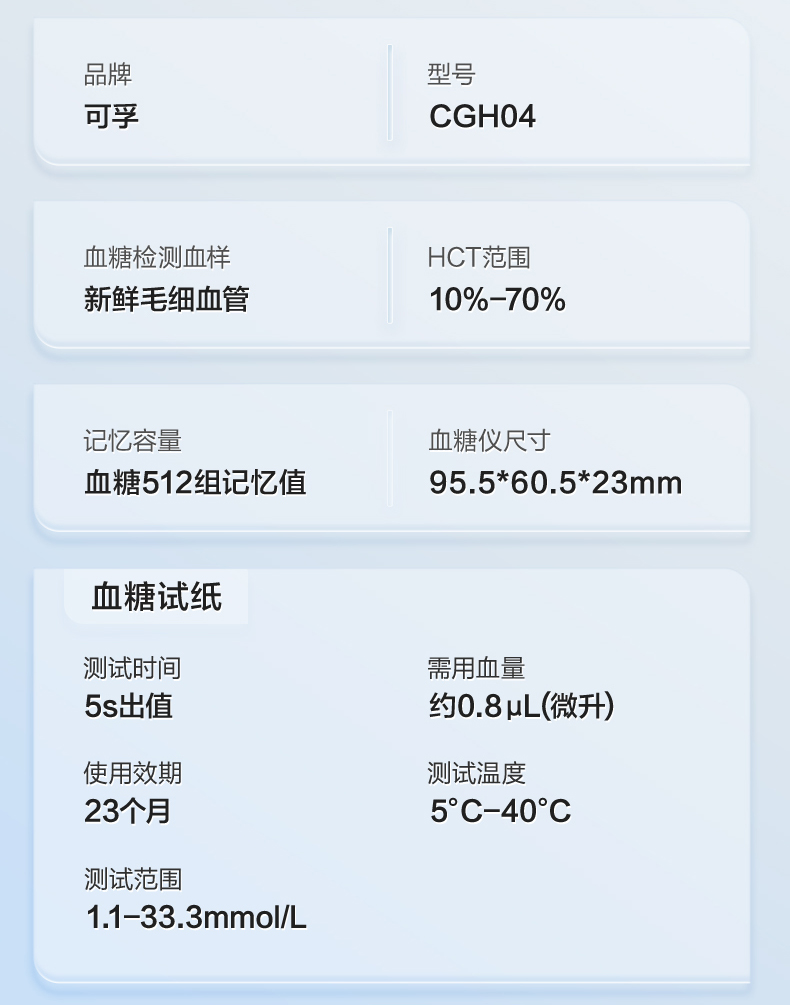

可孚新国标血糖测试仪家用测糖仪试纸官方旗舰店测血糖的仪器孕妇

Фото та опис товару